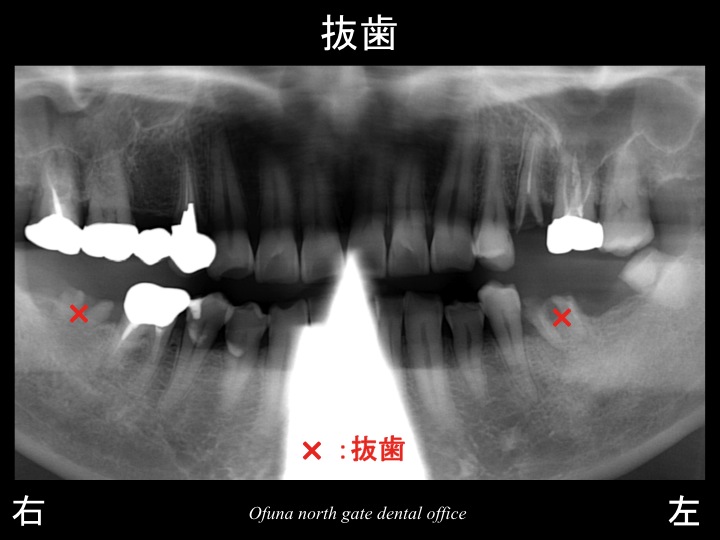

以下がインプラントの治療計画です。

今回の患者様は、下顎の左右奥歯が欠損したこの時点で

欠損部位にインプラント治療を行ったことが多きなポイントです。

欠損部にインプラントを埋入することにより、噛み合わせの安定が得られます。

これにより神経がない歯への負担を最小限にすることが可能になります。

簡単なケースでしたが、将来的なことを考えれば

インプラント治療は非常に有効な治療方法でした。